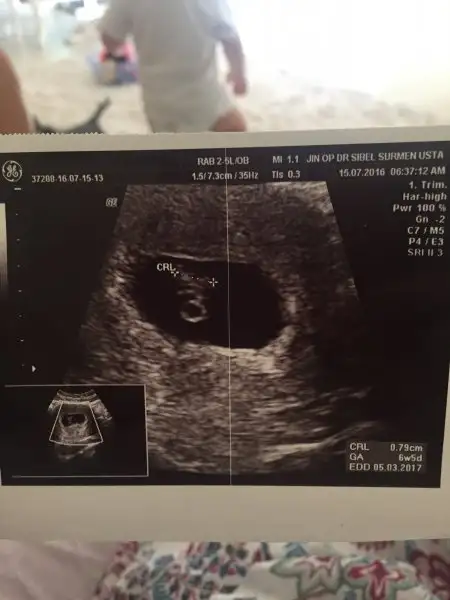

Altaki usg gibiydi benim minnoslarin konumu ve ikiside kiz rabbim saglikla nasip etsin insallah gonlundekiniMerhaba kızlar ilk usg 7+6 aşağıdaki ise bir önceki 6+4 her ikiside karından bana tahminde bulunabilir misinizHavalianne__ yine ben :) Xx

Merhaba kızlar ilk usg 7+6 aşağıdaki ise bir önceki 6+4 her ikiside karından bana tahminde bulunabilir misinizHavalianne__ yine ben :) Xx